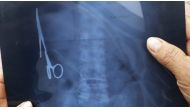

Surgical forceps removed from Vietnamese man after 18 years 04 Jan 2017 - 03:58 pm

An X-ray of Ma Van Nhat's stomach show where the scissors have been hiding for years.